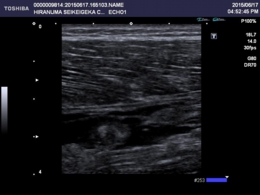

上記、中間広筋をエコー下で観察